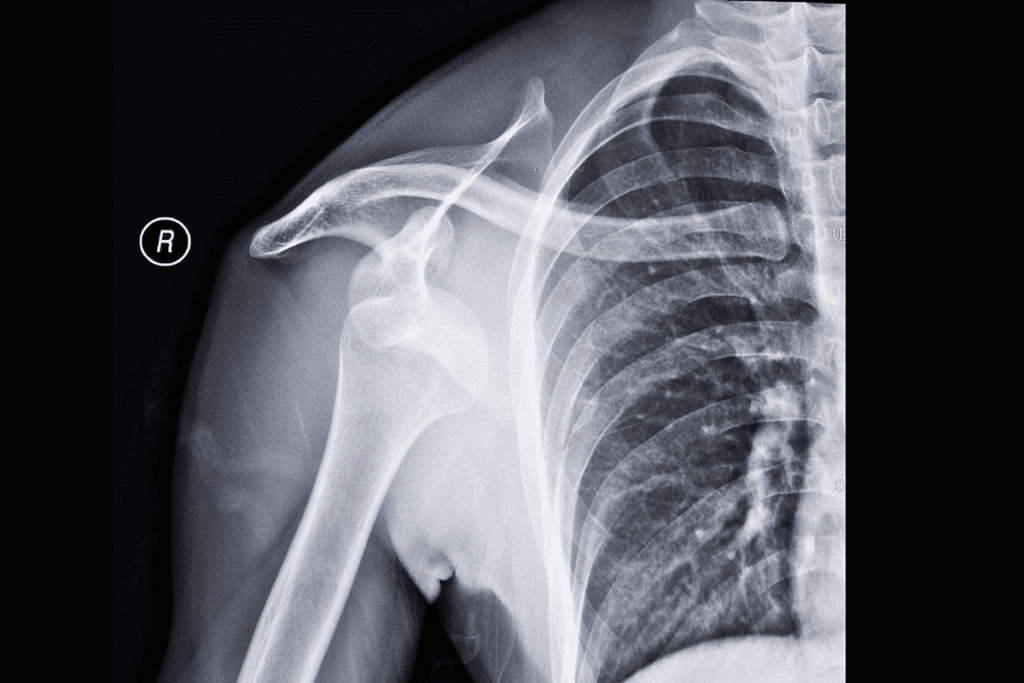

X-rays are often the first choice for shoulder dislocations. They check the humerus’s position and look for fractures. An X-ray can confirm the dislocation and spot complications early.

Magnetic Resonance Imaging (MRI) shows soft tissues like ligaments and tendons. MRI for shoulder dislocation is great for checking the rotator cuff and soft tissue injuries.

Computed Tomography (CT) scans give detailed views of cross-sections. They’re good for complex fractures or when MRI isn’t possible. CT scans for shoulder dislocation help see bony injuries and plan surgery.

In conclusion, X-rays, MRI, and CT scans are vital for diagnosing and treating shoulder dislocations. Each has its own use and benefits. Together, they help create a complete treatment plan.